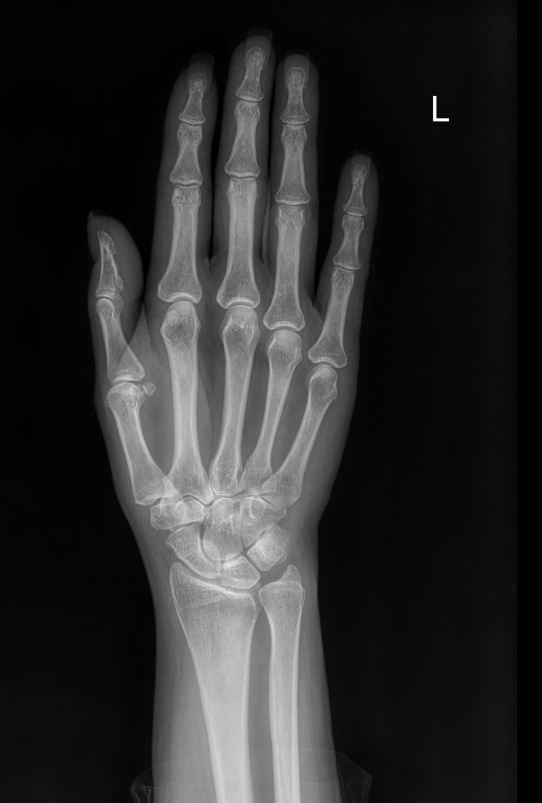

Кисти рук относятся к сложным анатомическим образованиям, в каждой из кистей находятся почти 3 десятка небольших костей. Они образуют мелкие суставы, к которым относятся и пястно-фаланговые.

Что можно увидеть на рентгене пястно-фаланговых суставов

• Суставную щель и ее деформацию;

• Суставные поверхности и их изменения;

• Состояние костной ткани ― участки уплотнения, разрастания, воспаления, разрежения и другой деформации;

• Травмы ― вывихи и переломы;

• Узлы и кисты.